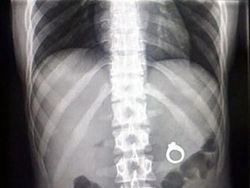

Cincinnya kok malah ditelan ya? (Foto: Brightside)